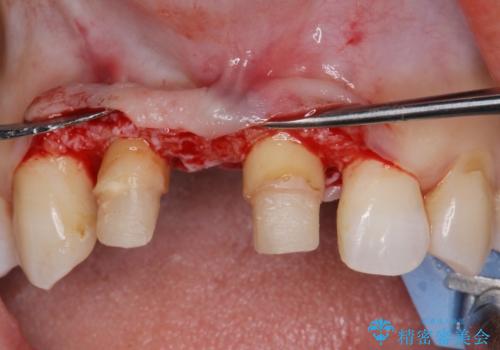

現在装着されているブリッジを除去したところ、歯ぐきよりも上に存在する歯質(縁上歯質)が少なく、土台の形態の悪さや不適合などさまざまな問題があります。

根管治療を行ったのち、歯周外科を行うことで、欠損部の歯ぐきの厚みを出し、縁上歯質を獲得することで、長期的な予後の見込めるブリッジを製作できる環境を整備していきます。